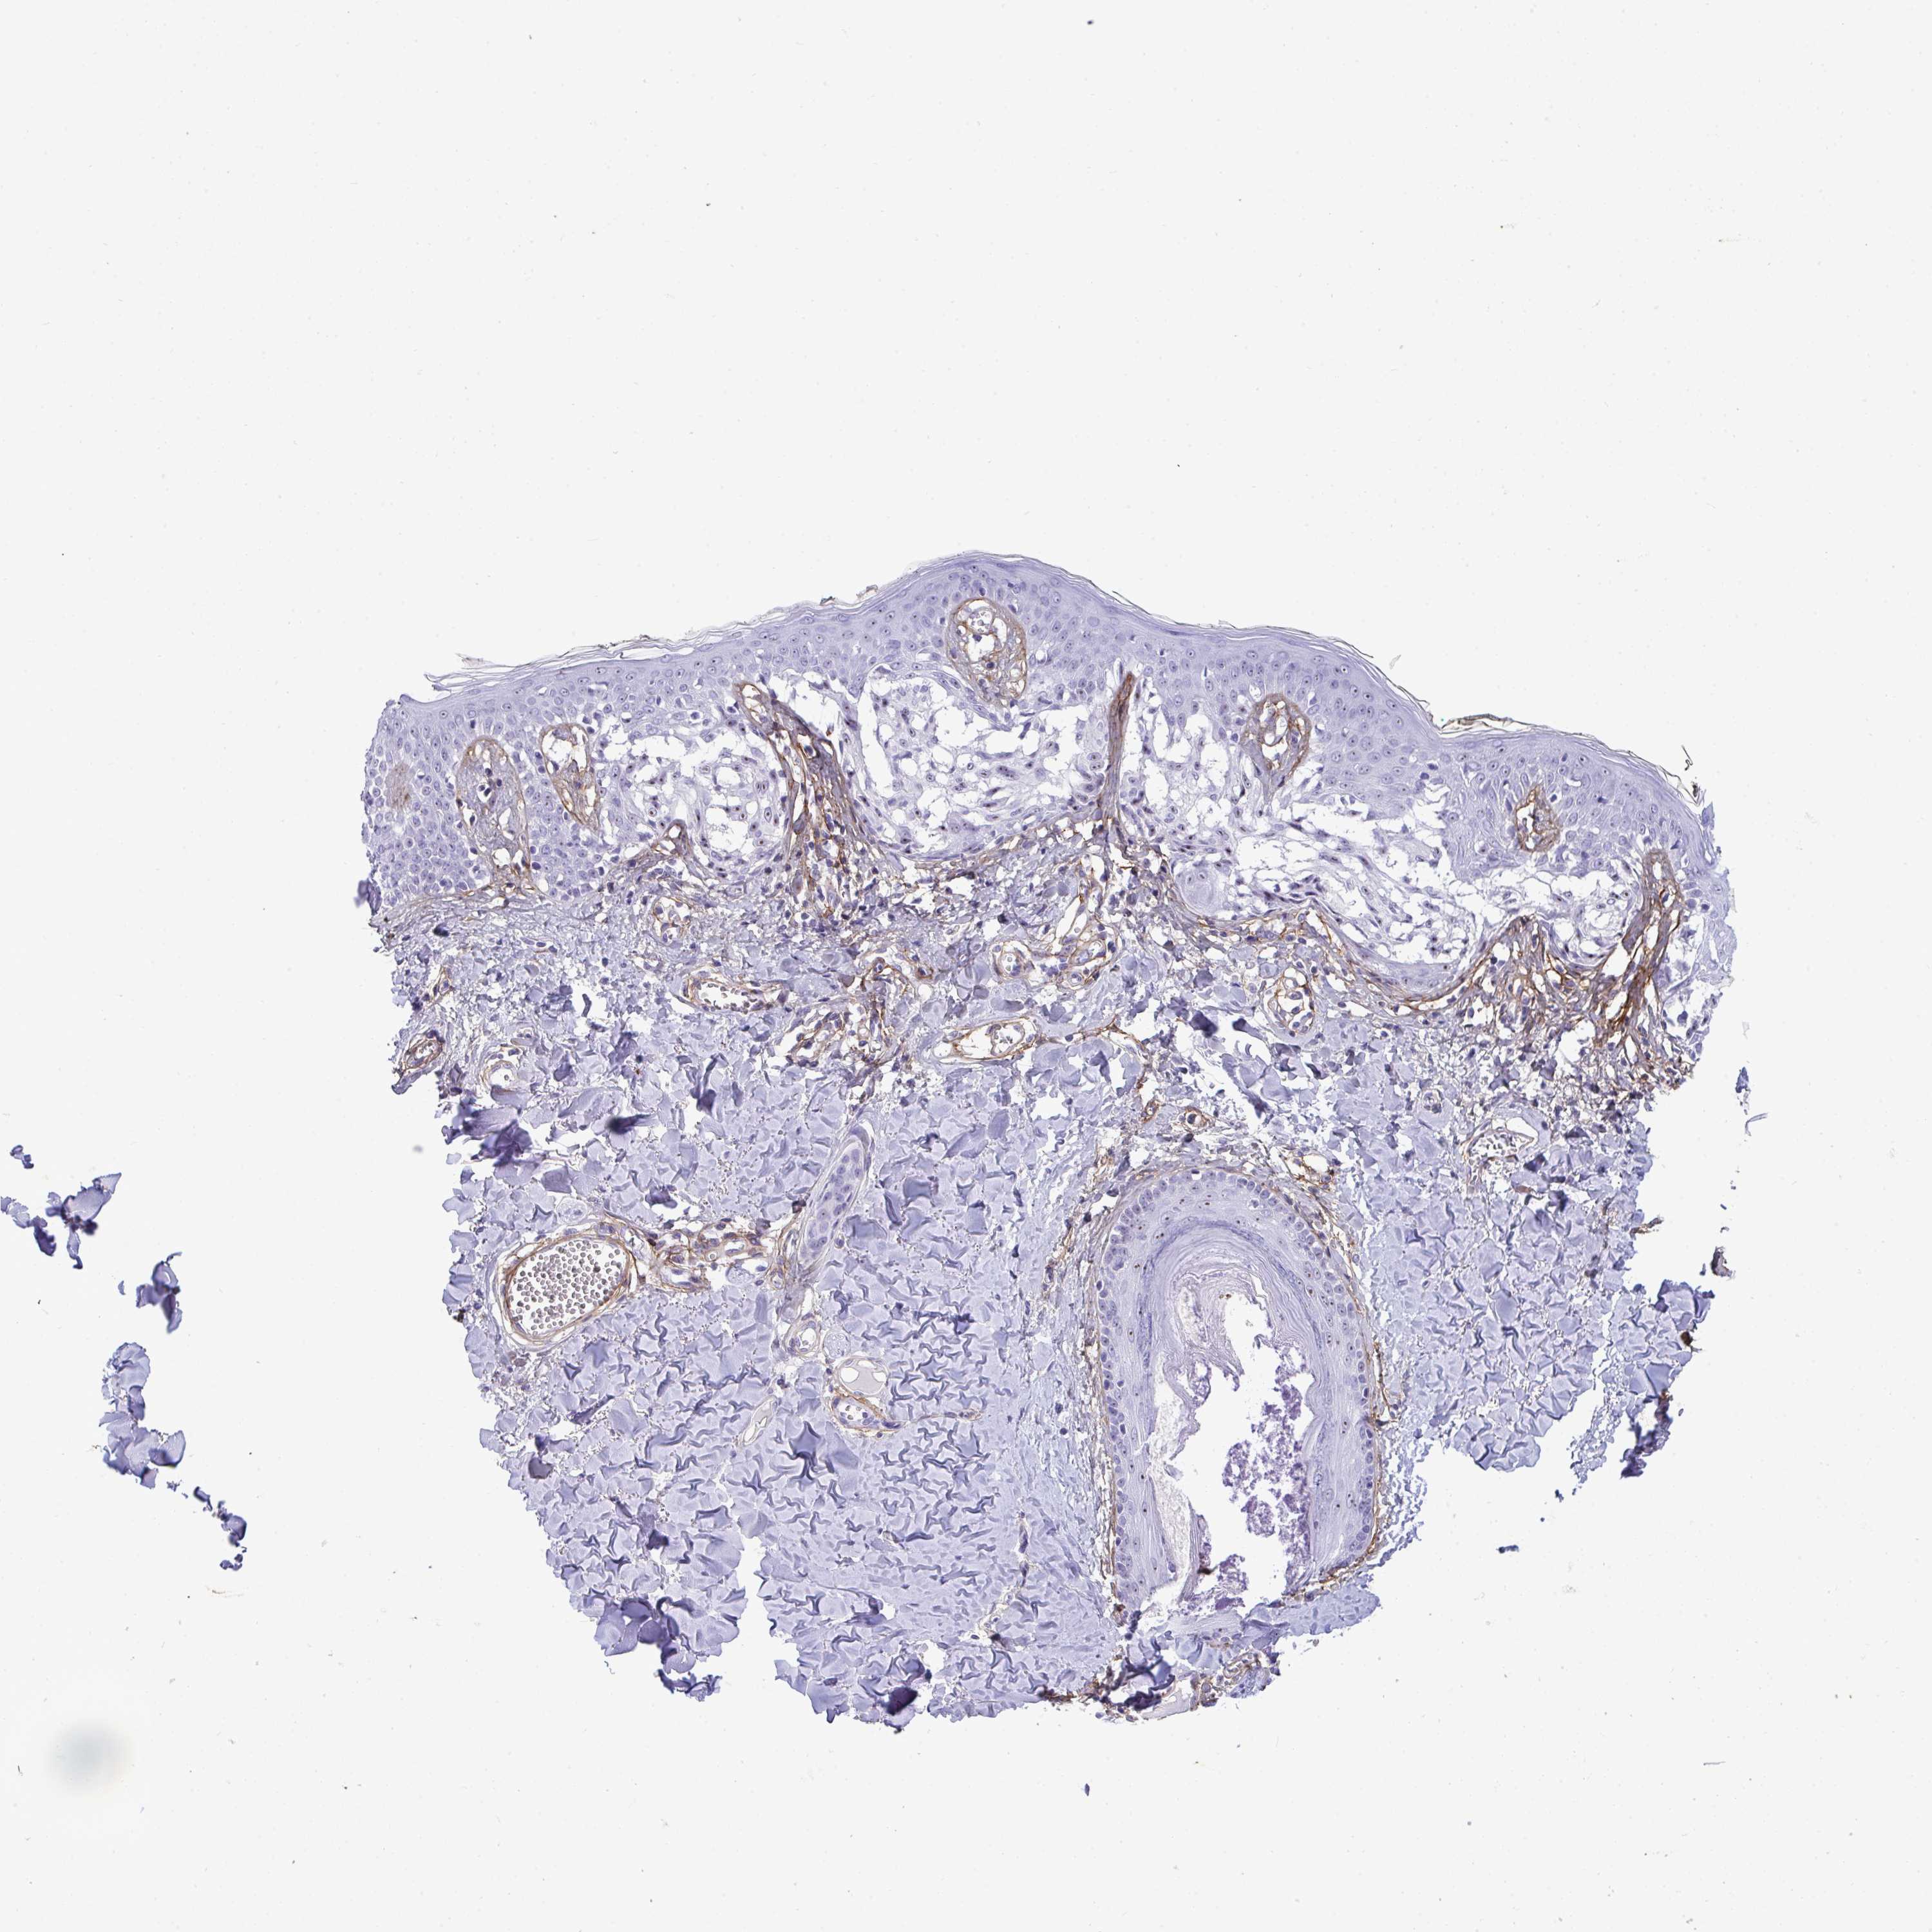

MELANOMA - Protein expressioni

A mouse-over function shows sample information and annotation data. Click on an image to view it in a full screen mode. Samples can be filtered based on level of antibody staining by selecting one or several of the following categories: high, medium, low and not detected. The assay and annotation is described here.

Note that samples used for immunohistochemistry by the Human Protein Atlas do not correspond to samples in the TCGA dataset.

Antibody stainingi

Antibody staining in the annotated cell types in the current human tissue is reported as not detected, low, medium, or high, based on conventional immunohistochemistry profiling in selected tissues. This score is based on the combination of the staining intensity and fraction of stained cells.

Each image is clickable and will lead to virtual microscopy that enables deeper exploration of all samples and also displays staining intensity scores, fraction scores and subcellular localization as well as patient and tissue information for each sample.

Antibody HPA058975

Staining

High

Medium

Low

Not detected

Intensity

Strong

Moderate

Weak

Negative

Quantity

>75%

75%-25%

<25%

None

Location

Nuclear

Cytoplasmic/membranous

Cytoplasmic/membranous,nuclear

Malignant melanoma, Metastatic site

Malignant melanoma, NOS